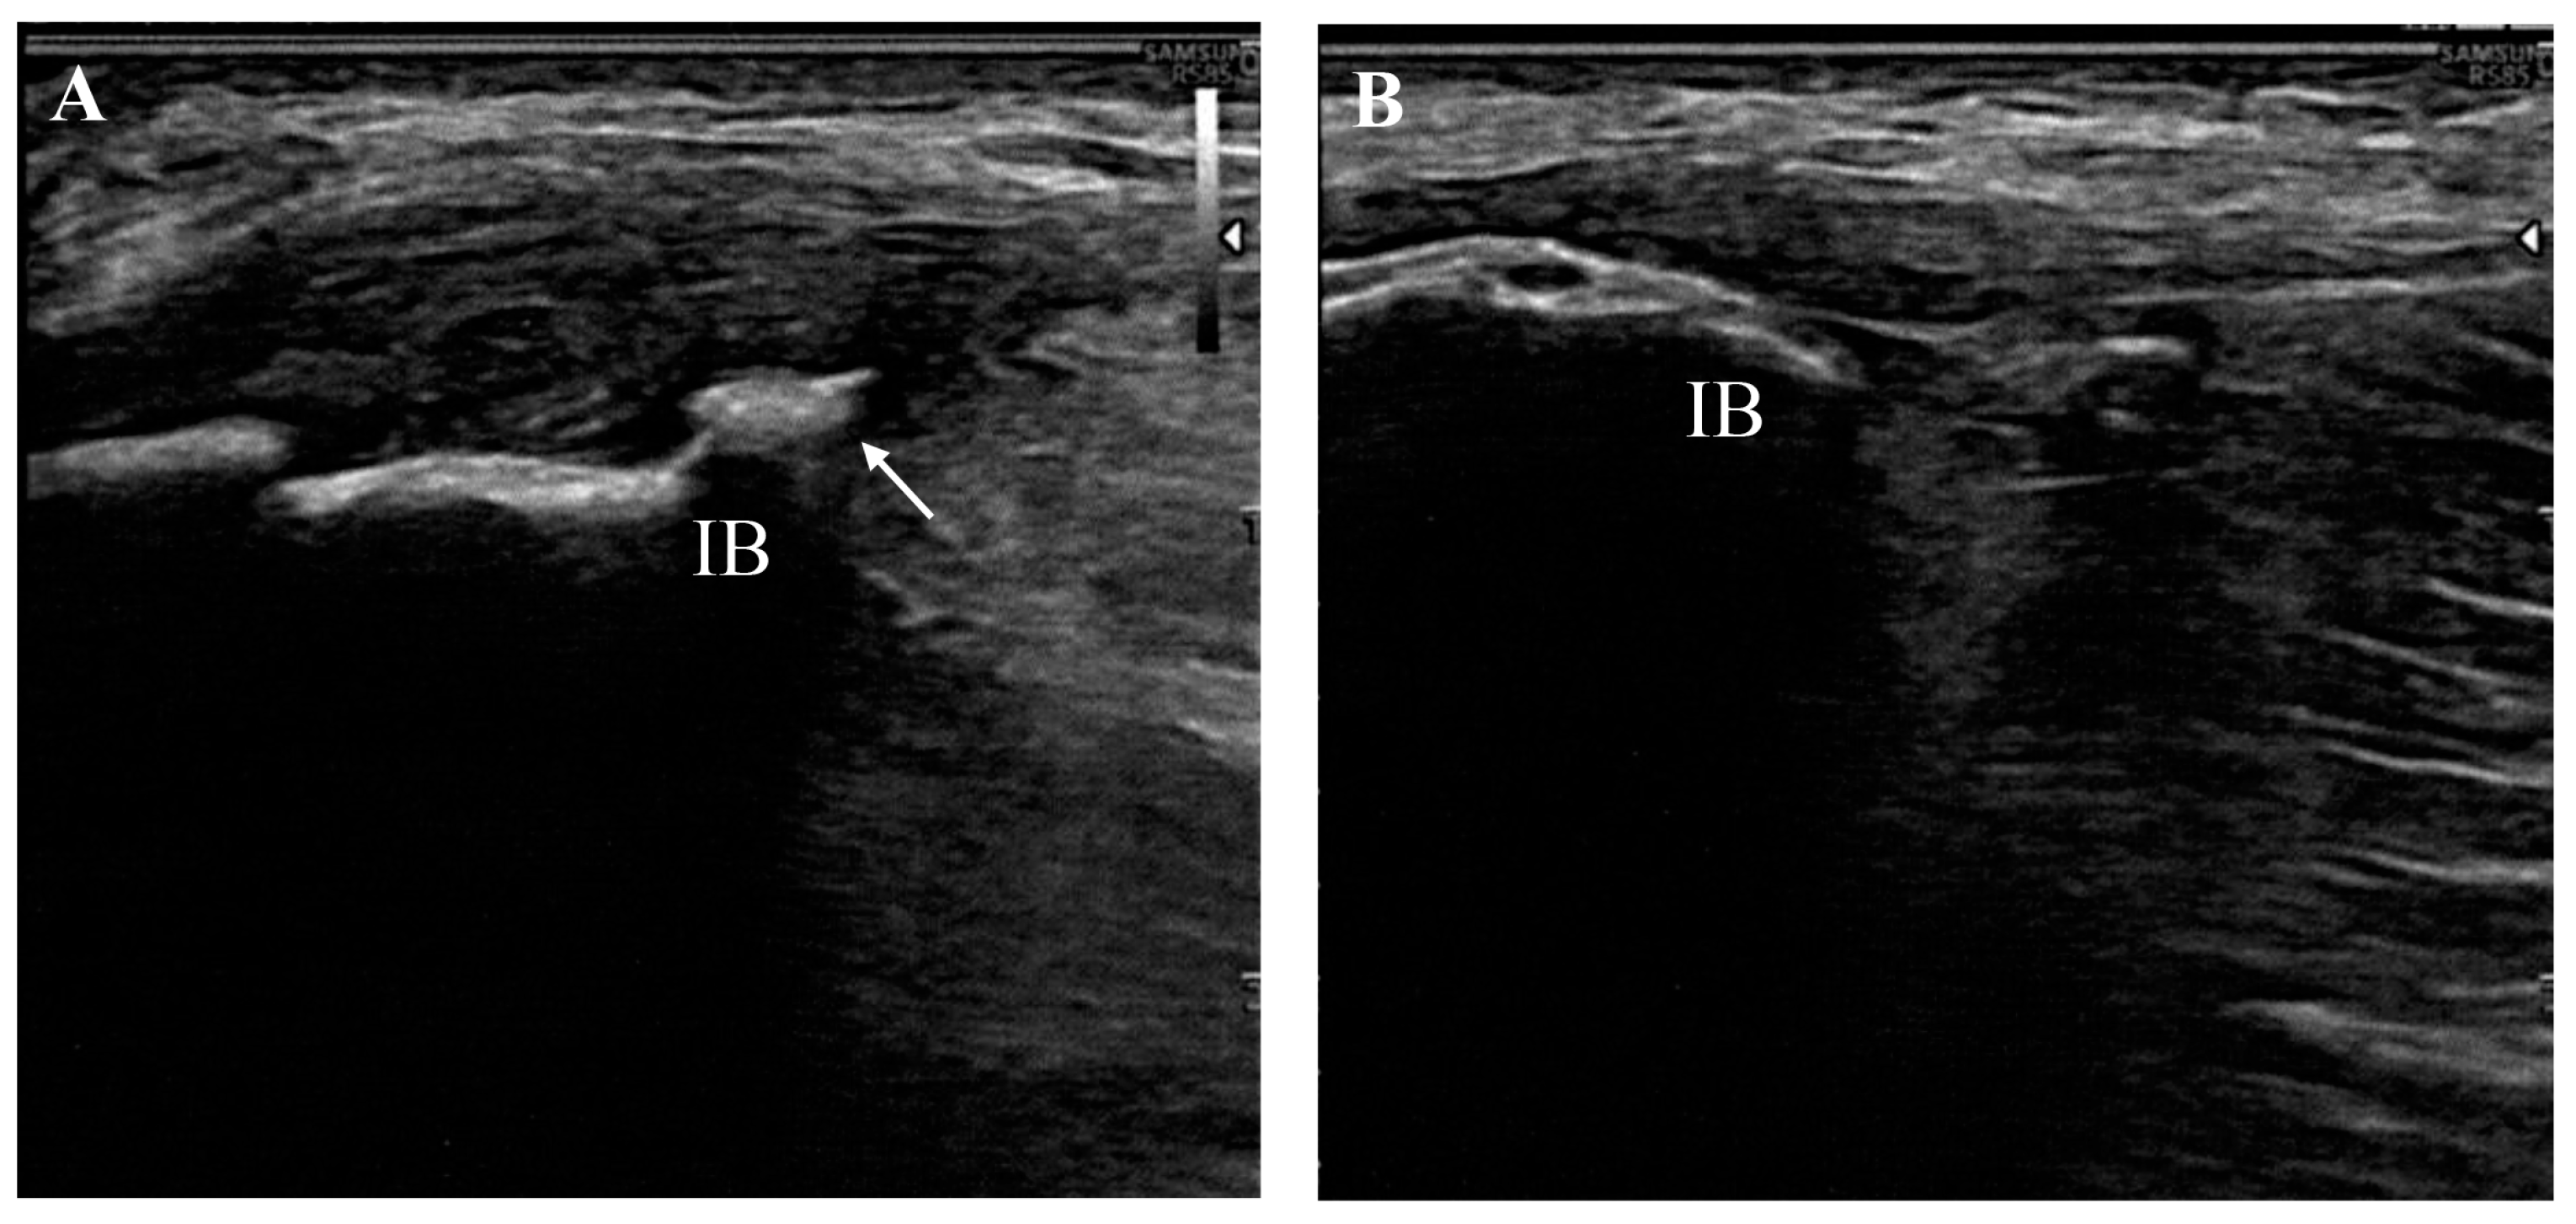

A chart review from two providers identified 14 consecutive patients (12 females and 2 males; mean age 64.36 ± 3.28 years) with ultrasound-confirmed gluteal tendinopathy who were treated with combined ESWT during the study period (Figure 1).

Figure 1.

Long-axis image of a tendinopathic gluteus medius tendon (A) with contralateral healthy comparison (B) showing hypoechoic thickening at the attachment onto the iliac bone (IB) and irregularities of the bone margin due to the presence of an enthesophyte (arrow).